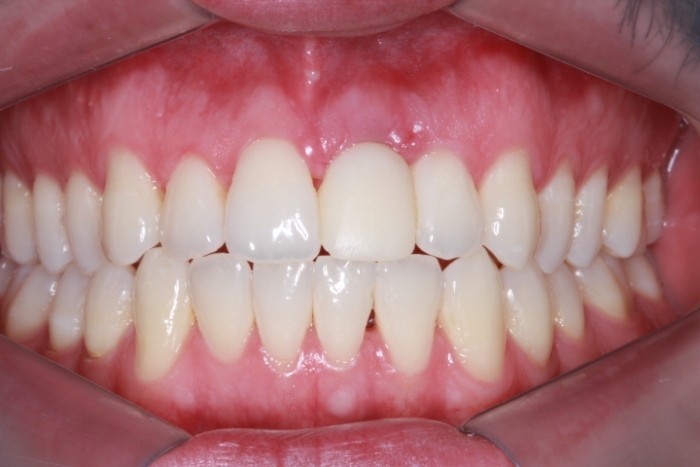

Foto Frontal com Protese definitiva 5 meses 21-11-15